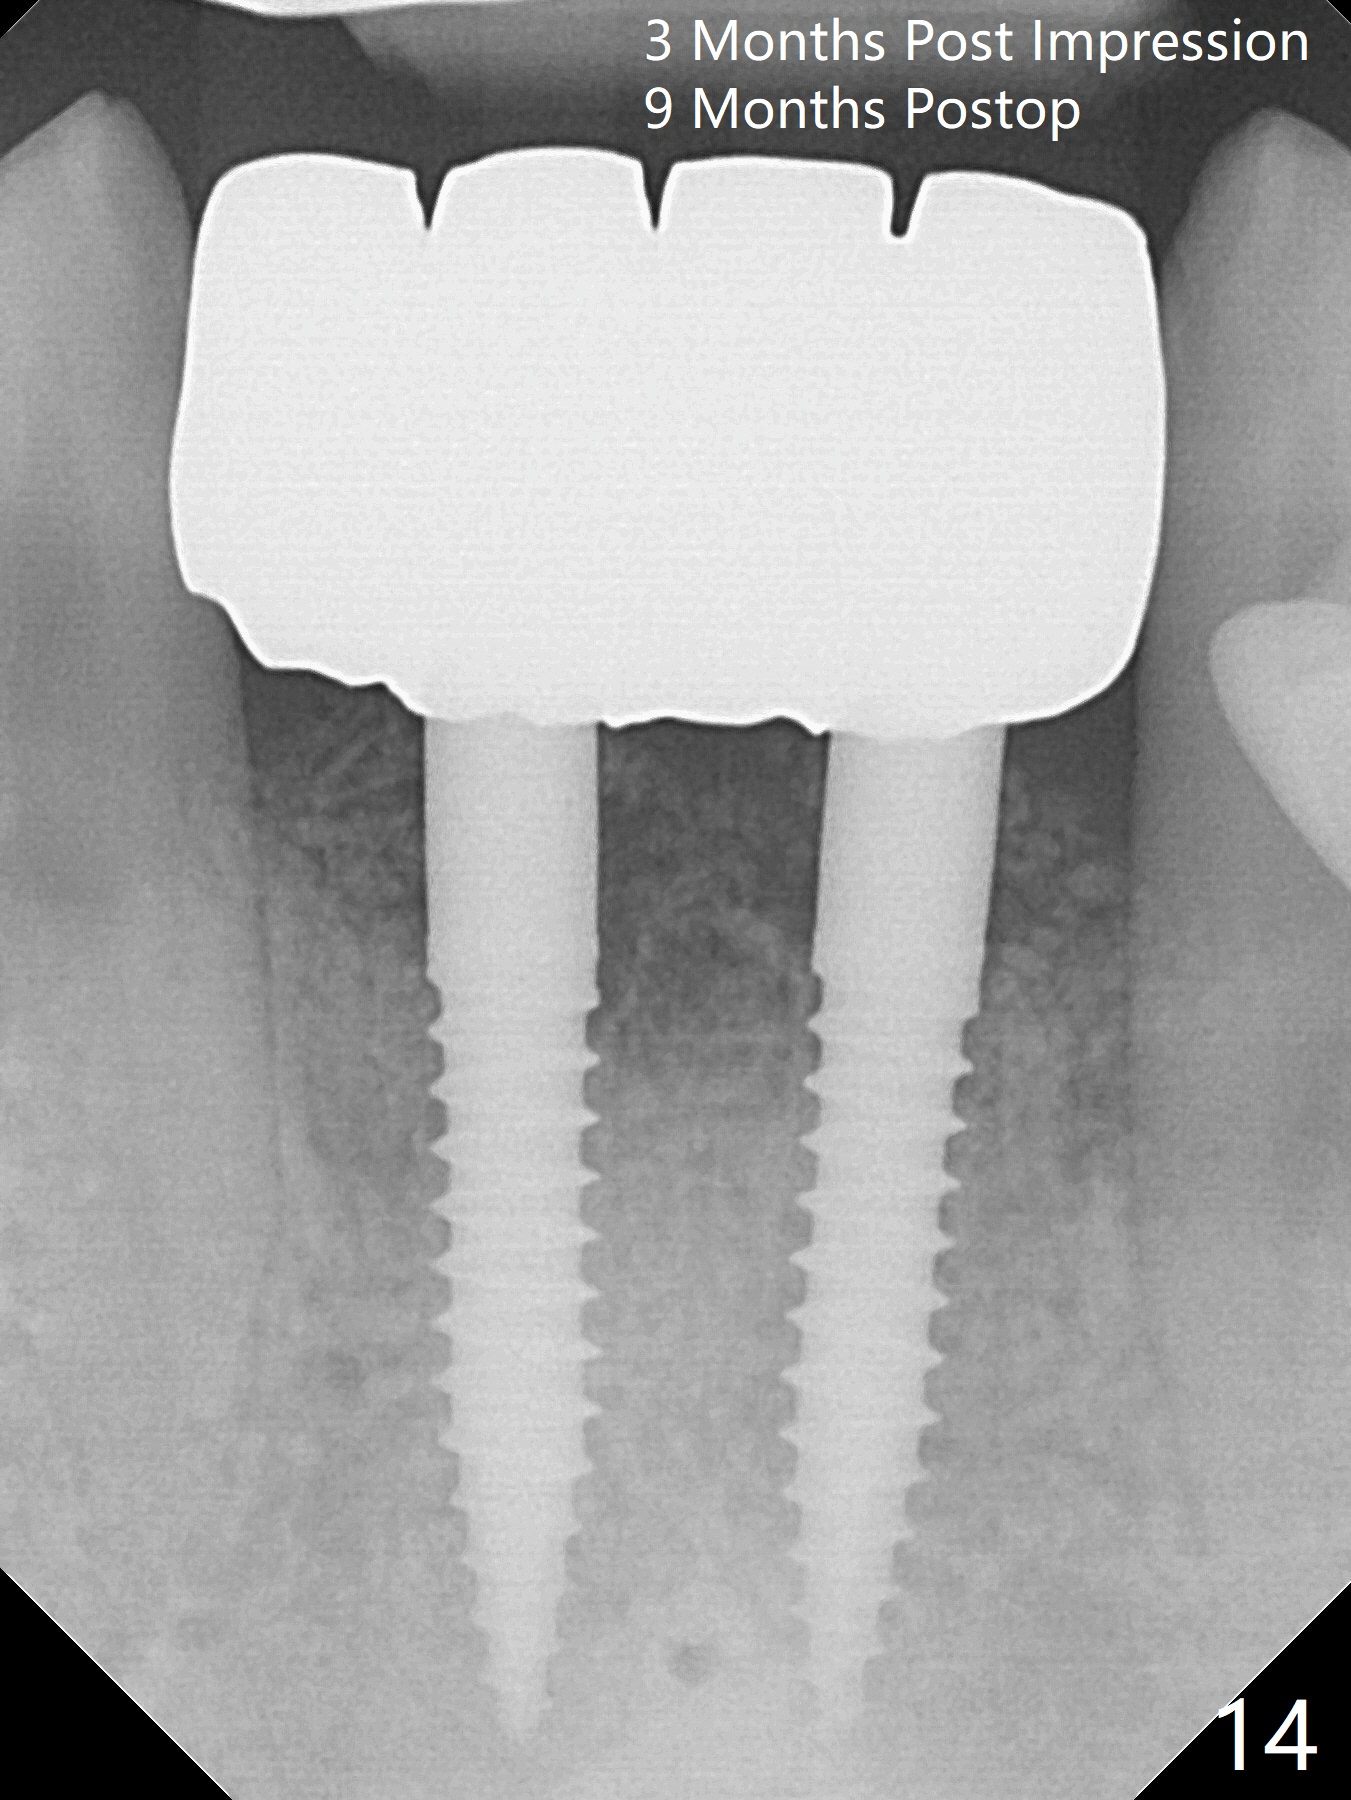

After extraction of 4 of the lower incisors, there are basically 2 sockets (#23/24 and 25/26), separated by the apparently midline bone (Fig.1 red line).  In spite of using Lindamann bur to move the 25/26 osteotomy mesially, a 3x14(2) mm dummy implant remains close to the tooth #27 (Fig.2).  The terminal branch of the Incisive Canal (<) is located between the lateral and central incisors.  A de novo osteotomy (Fig.3 (1.5 mm drill)) is made mesial to the original one (O).  While the 3x14(2) mm dummy implant is incompletely placed at #25/26, a 3x14(4) mm 1-piece one is placed at #23/24 (Fig.4).  Finally the same implant is placed at #25/26 with placement of mineralized cortical/cancellous bone (Fig.5 *).  When the large sockets are sutured, the supraerupted teeth #7-9 touch the lower gingiva (Fig.6).  The incisal edge is reduced for clearance (Fig.7).  Periodontal dressing is less likely to be dislodged with the incisal edge reduction (Fig.8,9).  A provisional FPD is fabricated 1 week postop.  Hard (Fig.10) and soft (Fig.11,12) tissues heal 5.5 months postop.  The patient returns for crown cementation 3 months post impression (9 months postop, Fig.13,14).